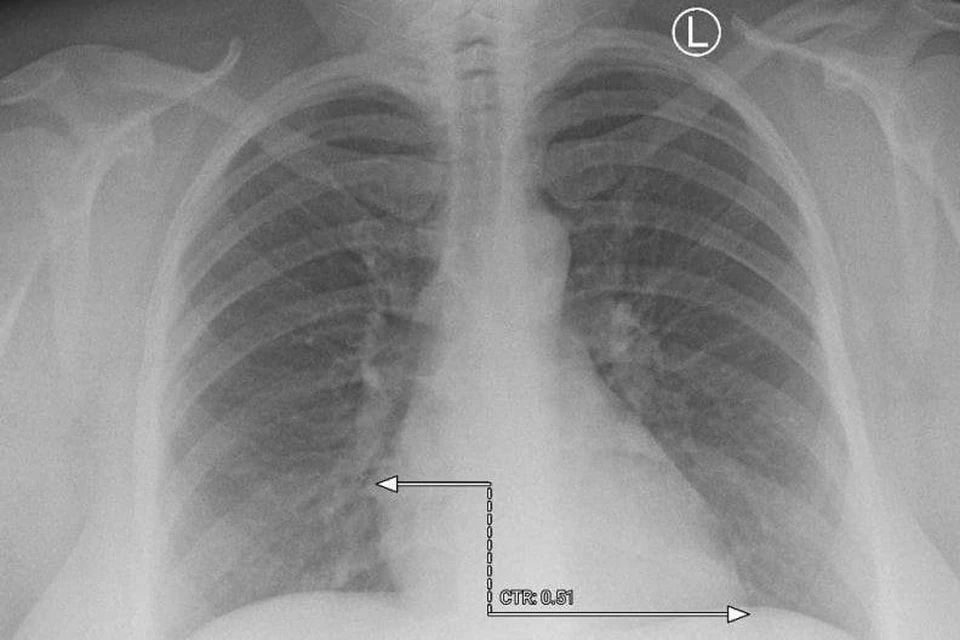

Врачи городской больницы №21 города Уфа направили на платформу «МосМедИИ» рентген органов грудной клетки пациента и спустя минуту цифровой помощник предоставил заключение. Искусственный интеллект интерпретировал изображение, разметил зоны патологических очагов и выдал протокол исследования.

Получившийся результат Айрат Рахматуллин назвал большим прорывом в области цифровизации здравоохранения. По его мнению, искусственный интеллект поможет быстрее изучать КТ, МРТ, рентгенснимки, флюорографию и ангиографию.

– Стоит отметить, что последнее слово все же будет оставаться за врачом. До конца года планируется расширить как количество медицинских организаций, так и количество ИИ-сервисов, используемых республикой на «МосМедИИ», – заявил руководитель Минздрава республики.